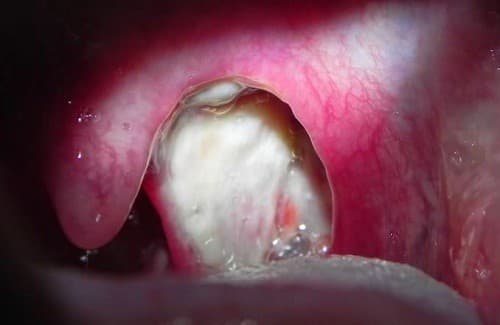

Viêm amidan hốc mủ Chất bã đậu tiết ra

Viêm amidan hốc mủ là thể viêm amidan mạn tính. Chất bã đậu tiết ra nhiều hơn bình thường rồi ứ đọng trong các hốc amidan gây ra các chấm trắng trên amidan. 1. Viêm amidan hốc mủ là gì? Amidan là một bộ phận của cơ thể, nằm ở vị trí cầu nối giữa […]